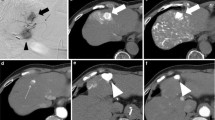

Measurement of BOASP and selective B-TACE were successfully performed in all 43 treatments. The dose of lipiodol ranged 0.5–10 mL (4.5 ± 3.5). The contrast material did not stay, but the arterial flow beyond the occluded portion was maintained on DSA and fluoroscopy in all treatments even after the balloon was inflated. At the beginning of LE infusion, pulsatile flow of the LE droplets into vessels supplying the HCC nodule and those supplying the liver parenchyma was noted in all 43 treatments. After LE droplets reached the peripheral thin vessels supplying the nontumorous liver parenchyma, two flow patterns were observed. The LE inflow into the nontumorous liver parenchyma ceased after the peripheral thin vessels were filled with LE in 39 treatments (group 1) (Figs. 2, 3) but did not cease in four treatments (group 2) (Fig. 4). In all 43 treatments, the LE droplets continued to flow into the HCC nodule. Thus, LE accumulation in the HCC nodule was dense in group 1 (Figs. 2, 3) but not in group 2 (Fig. 4). The BOASP in group 1 was 33.8 ± 12.8 mmHg (range 13–64) and that in group 2 was 92.3 ± 7.4 mmHg (range 83–100). The BOASP in group 1 was lower than that in group 2, with a statistically significant difference (p = 0.00004, Welch’s t test) (Fig. 5). The LECHL ratio was 18.3 ± 13.9 (range 2.9–54.2) in group 1 and 2.6 ± 1.1 (range 1.7–4.2) in group 2. There was a statistically significant difference between the groups (p = 0.000034, Welch’s t test) (Fig. 6).

Selective B-TACE without depiction of collateral artery in the same case as that shown in Fig. 1. A The microballoon catheter was placed at A7 for selective B-TACE (arrow). Peripheral tumor feeding arteries (arrowheads) were thinner than the 3F (1 mm) shaft of the microballoon catheter (white arrow). B At the beginning of LE infusion, LE was distributed into the peripheral vessels supplying liver parenchyma (arrowheads) and those supplying HCC nodule (arrows). C The LE inflow into the liver parenchyma soon ceased (arrowheads), while that into the HCC nodule (arrows) continued, and LE was densely accumulated in HCC nodule. A LE droplet was always present at the tip of the microballoon catheter (white arrow B, C). D Finally, fragmented porous gelatin particles were embolized into arterial branches (arrows), and selective B-TACE was completed

Selective B-TACE with depiction of collateral artery. A The celiac artery was obstructed, and the microballoon catheter was placed at the posterior segment artery (arrowhead) via the superior mesenteric artery (arrow). The main feeding artery was A7 (white arrow), and thin feeding arteries originated from A6 (white arrowhead). These thin feeding arteries were thinner than the 3F (1 mm) shaft of the microballoon catheter (large arrow). B At the beginning of LE infusion, LE droplets were distributed into the peripheral vessels supplying liver parenchyma (arrowheads) and HCC nodule (arrows). The LE inflow into the liver parenchyma (arrowheads) soon ceased while that into the HCC nodule continued (arrows), and LE was densely accumulated in HCC nodule. An LE droplet present at the tip of the microcatheter during LE infusion (white arrow B, C). D The arterial branches of the posterior segment were embolized and filled with fragmented porous gelatin particles (arrows). At the end of gelatin embolization, A8 was depicted on fluoroscopy. E The microballoon catheter was placed at A8 (arrowhead), and DSA was performed via the right anterior oblique view to escape the overlap of HCC filled with LE on collateral artery. DSA revealed anastomosis vessel (arrow) between A8 and A7 (white arrow), and A8 was embolized with fragmented porous gelatin particles. F CT obtained immediately after selective B-TACE revealed dense LE accumulation in HCC (large circle). G Slight LE accumulation in liver parenchyma of the embolized region was also evident (circle)

Selective B-TACE without dense LE accumulation. A DSA of the celiac artery demonstrated an HCC nodule (white arrowheads) in the medial segment, and selective B-TACE was carried out while placing the microballoon catheter at A4 (white arrow). LE continued to flow both into the liver parenchyma and HCC nodule, and no dense LE accumulation in HCC nodule was noted. B DSA after selective B-TACE revealed anastomotic vessels for both the left (arrow) and right hepatic arteries (arrowhead). C CT obtained immediately after selective B-TACE revealed intermediate LE accumulation in HCC (arrow) and liver parenchyma of the embolized region (arrowheads)